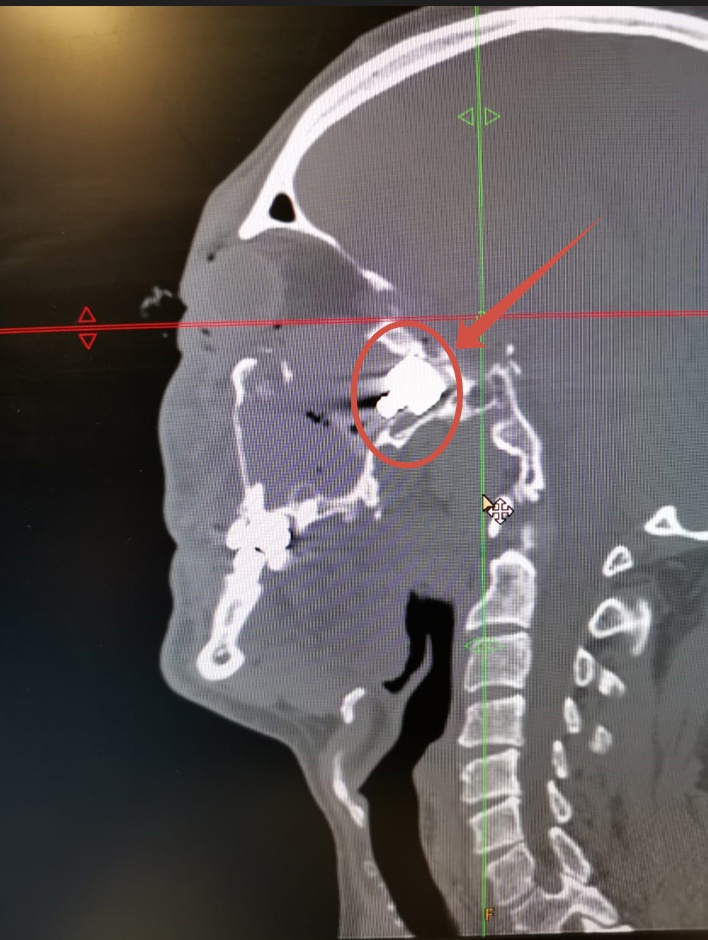

Пациента доставили в больницу ночью перед Новым годом из Хлевенского района. Как рассказал GOROD48 заведующий оториноларингологическим отделением Александр Медвежинский, который и провел операцию, в мужчину стреляли из травматического пистолета, пуля прошла под левым глазом и застряла у основания черепа.

Ночью врачи оперативно собрали профессиональную команду для сложнейшей операции. Оториноларингологии удалили пулю из глубоких структур лицевого скелета головы эндоскопическим путём, то есть без разреза. Они спасли пациенту жизнь, пуля в любой момент могла сместиться и задеть жизненно-важные органы, или вызвать заражение.